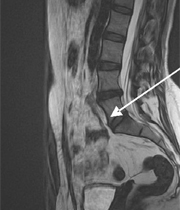

El traumatólogo José Miguel Donoso reveló a Una Nueva Mañana los beneficios de un nuevo procedimiento de cirugía endoscópica para tratar las hernias lumbares o hernias de núcleo pulposo y extraerlas de manera menos invasiva.

ImagenSegún Donoso, el procedimiento implica "que a través de un tubo con una cámara podemos llegar al interior del cuerpo y reparar o solucionar problemas que normalmente habrían requerido una cirugía abierta".

Considerando esto, "lo que se hace es introducir un tubo de 8 milímetros, que tiene un tamaño suficiente para ingresar en la columna directamente, tomar la hernia y sacarla. Por lo tanto, evitamos todo el daño innecesario que se hace en la cirugía abierta para hacer un procedimiento con el mismo resultado".